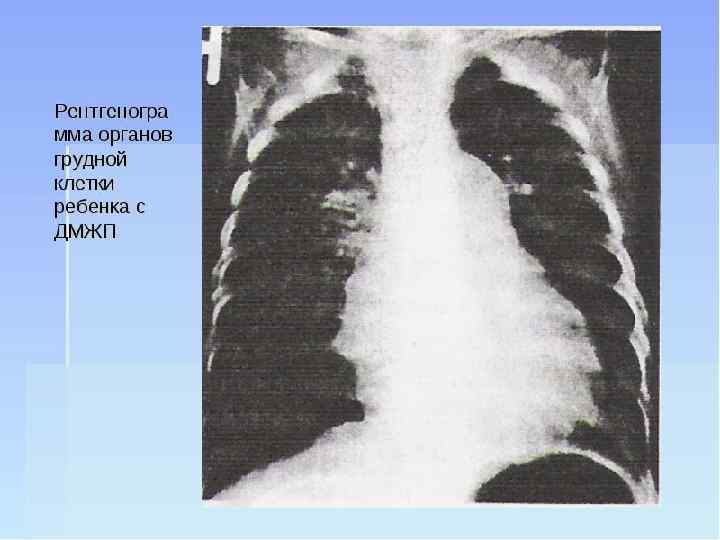

ДИАГНОСТИКА систолический шум слева и справа от грудины. ЭКГ признаки перегрузки левых отделов сердца, за исключением пациентов со стенозом лёгочной артерии (преобладает нагрузка на ПЖ). комбинированная гипертрофия желудочков, при развитии синдрома Эйзенменгера — выраженную гипертрофию ПЖ рентгенологическая картина представлены усилением лёгочного рисунка, а также увеличением тени сердца